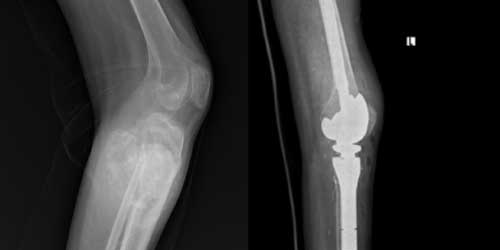

Omurga metastazı, kanserin ilk olarak iç organlarda gelişip daha sonra omurga kemiklerine yayılması sonucu oluşan bir durumdur. Çoğunlukla kan yoluyla sıçrayan bu tür metastaz, hastalarda sırt ve bel ağrısı gibi şikayetlerle kendini gösterir. Erken teşhis ve uygun tedavi yöntemleri, hastaların yaşam kalitesini artırmada kritik bir rol oynar.

Tedavide başarıyı artıran en önemli etkenlerden biri ameliyat öncesi iyi bir hazırlık ve cerrahi planlama yapmaktır. Her şeyden önce tanı doğru konmalı. Bunun için hasta iyi dinlenip, detaylı muayene edildikten sonra tetkikleri dikkatli incelenmelidir.

Her ameliyatın olduğu gibi kemik ve yumuşak doku tümör ameliyatlarının da riskleri vardır. Bu riskleri genel ve yapılan ameliyata özgü olmak üzere kabaca iki başlık halinde gruplandırabiliriz. Öncelikle anestezi ile ilgili risklerin anestezi uzmanı tarafından (...)

Ameliyat sonrası takip ve kontrol hastanın ameliyat masasında uyanması ile başlar. Özellikle damar ve veya siniri ilgilendiren ameliyatlarda hasta ameliyat masasından alınmadan ekstremitenin dolaşımı ve ilgili sinirin fonksiyonu kontrol edilir.